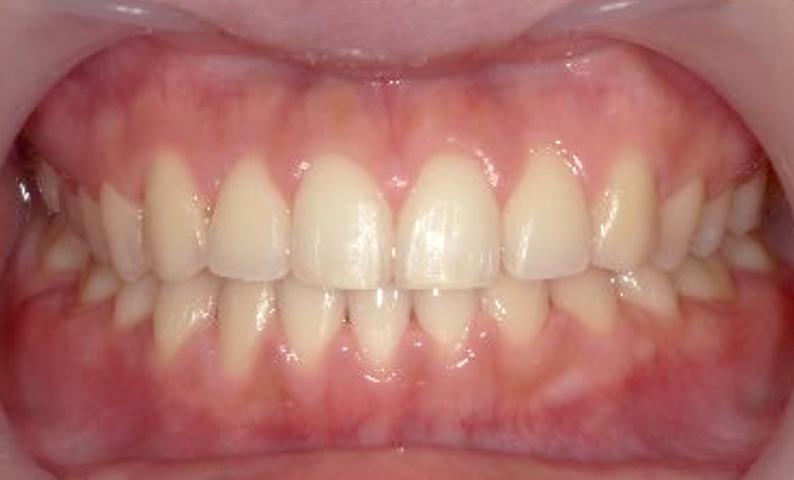

| 治療前 | 治療後 |

|---|---|

|